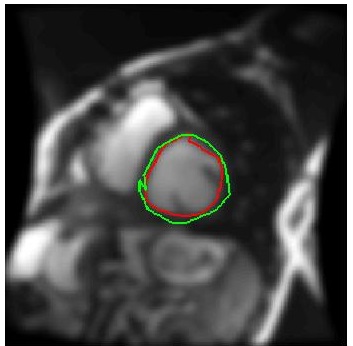

We train our ISR network from scratch. Each volume slice is treated as a separate image and transformed by random rotation and translation. We rotate the images between in steps of . For each rotation we translate the image by pixels in steps of . Thus on an average we get transformation for each image. Thus an average of slices per image gives a total of cardiac MR images. We show results on ISR for scale factor . Results for ISR are summarized in Tables 5. Following the approach for retinal landmark and pathology segmentation, we also show results for cardiac left ventricle segmentation (Table 6). For each segmentation approach we employ UNets as the segmentation framework and show results for different super-resolution methods as well as the low-resolution images (). Dice metric values for segmentation accuracy are shown in each case. Similar to retinal pathology segmentation we extract a patch covering the pathology and apply super-resolution for scale factors .

Figure 6 shows results for segmenting the cardiac LV from MRI. For each case we present results on the original HR images, SR images obtained by each of the methods being compared and also when using the LR images (scale factor ). It is quite obvious that the LR images are very fuzzy and don’t give accurate information on the anatomical boundaries. On the other hand the SR images from our method can predict a highly accurate reconstruction of the actual image. Other ISR methods show some degree of blur in the SR images. It is remarkable that deep neural network based methods are able to reconstruct original high quality images despite limited information in LR images. This is possible because of the ability of the generator networks to learn the relation between HR and LR images.